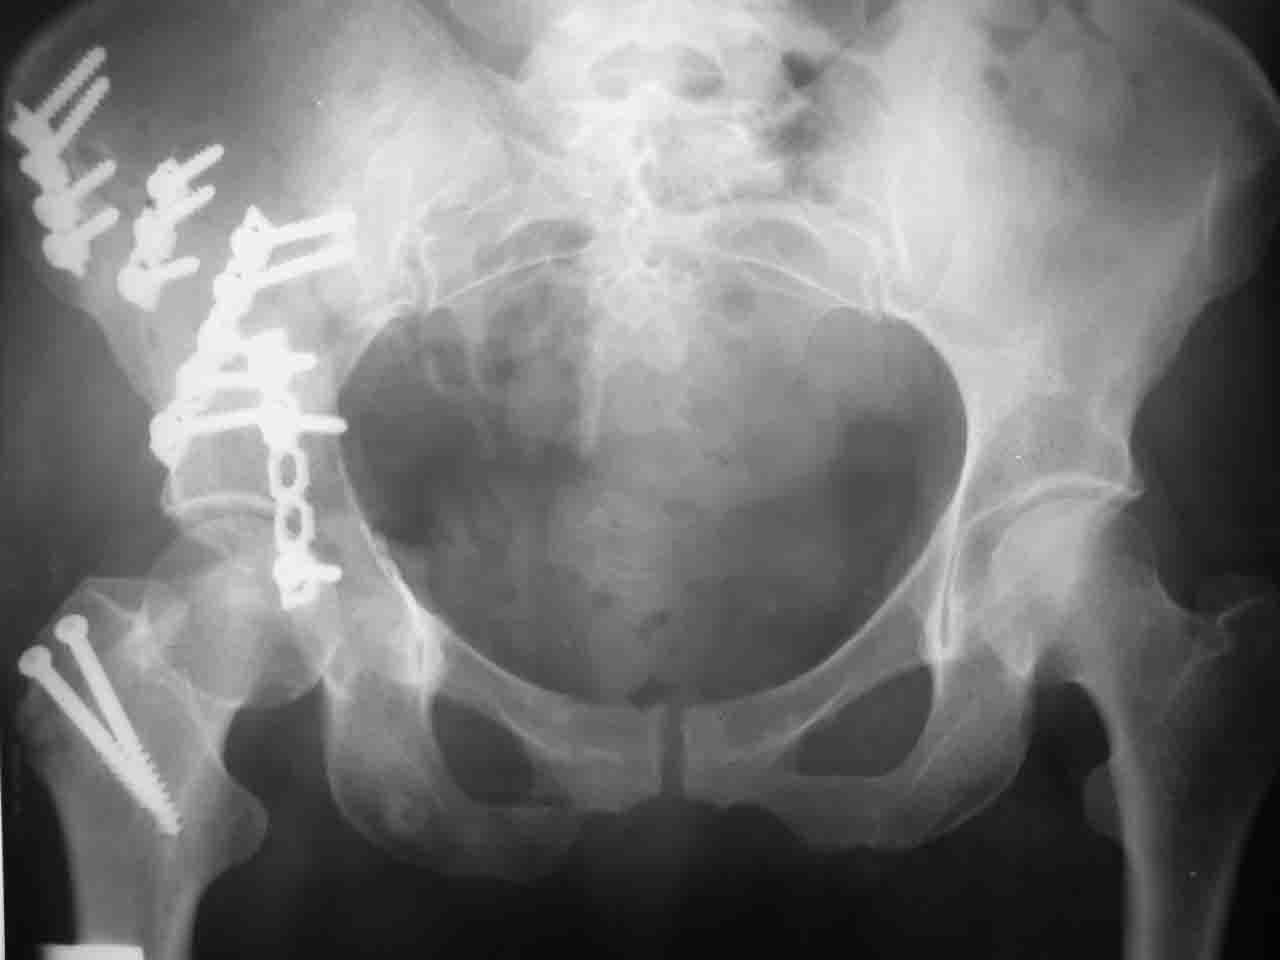

А какой отдел вертлужной впадины более важен передний или задний? Чем был обусловлен выбор доступа к суставу? Проще говоря, почему вы пошли передним доступом на двухколонный перелом? Мне понятны ваши сомнения, когда не удется сделать все что хотелось бы. В данном случае доступ должен быть чрезвертельным боковым (как и советовал Рунков) или двумя доступами.

Интерес к реконструкции вертлужной впадины у меня появился довольно-таки давно, но до недавнего времени как-то не ощущалась готовность к практической реализации, а местный подход достаточно консервативен - перелом срастется,

а далее будет видно. Такую точку зрения я не разделяю, поэтому через конференции,ортофорум и свои случаи пытаюсь практически и теоретически *продвинуть* для себя тему реконструкции вертлужной впадины.

Логика подсказывает, что все-таки лучше иметь анатомически полноценную впадину, хотя ранее упоминалось состояние вторичной конгруэнтности и одно наблюдение у меня есть, когда у больного с полностью нарушенной анатомией впадины и подвывихом головки бедра кзади и кверху боли отсутствовали при относительно достаточном для стиля жизни больного объёме движений. Но это только одно наблюдение и кроме перелома впадины у этогобольного была и тяжелая ЧМТ в анамнезе. Основываясь на формулировке структуры ацетабулюм Э. Летурнеля - как перевернутой буквы Y, впадина для полноценной функции сустава должна иметь сферичность, соответствующую размеру головки бедра и если один из компонентов в дефиците, то функциональные последствия рано или поздно проявятся.

Сложностью, ассоциативностью характера перелома, я бы с радостью воспользовался мининвазивной перкутанной фиксацией винтами, но боюсь, что результат был бы ещё хуже, техникой непрямой репозиции перелома не владею, поэтому пытаясь получить анатомичную впадину приходится широко открывать, по крайней мере пока, а дальше буду пытаться уменьшать пространство...

> передним доступом на двухколонный перелом?

Илеофеморальный доступ не совсем передний и сравнительно с илеоингвинальным, и Кохера-Лангенбека открывает весь наружный таз кроме самых передних отделов лонных костей, фиксацию которых я не ставил в задачу. Обширность диссекции, большая длительность операции и более высокий риск гетерооссификации - отрицательные моменты в обмен на возможность легче ориентироваться.

Вопрос доступа к вертлужной впадине при остеосинтезе задача не простая. Конечно, у Летурнеля и Тайла всё давно описано, нам остается только брать на вооружение. Но сами понимаете, что не бывает двух одинаковых ситуаций, поэтому в каждом случае вопрос решается сугубо индивидуально. Наша главная цель - восстановить анатомию с нанесением минимальной дополнительной травмы тазобедреннному суставу, думаю с этим никто не поспорит. Расширенный илиофеморальный доступ уж слишком травматичен (как сказал один коллега "таз лежит отдельно, больной отдельно").Стоит ли делать из пациента анатомический препарат для того чтобы легче ориентироваться. Да и нужно ли собирать всю "мозаику"? Мы применяли при таких операциях своеобразную операционную хитрость - сначала устраняли грубое смещение крыла под гребнем с фиксацией так называемой "плавающей" пластиной (временно фиксированной на двух винтах)- доступ или продлевали боковой, или делали небольшой дополнительный разрез над гребнем. Это позволяло устранить грубое смещение и захождение отломков тела повздошной кости, что значительно облегчало репозицию и остеосинтез впадины над сводом. Основное внимание конечно же уделяли нагружаемому задне-верхнему отделу. Сообщите ваш адрес, пришлю схемы и рентгенограммы.